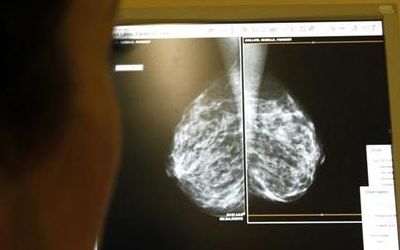

وثار الجدل حول فحص الثدي بالأشعة في أواخر عام 2009 عندما قررت مجموعة تمولها الحكومة من الخبراء المستقلين تغيير توصياتها.

وبدلا من تقديم مشورة فحص الثدي بالاشعة سنويا لجميع النساء في سن الأربعين فأكثر قالت فرقة الخدمات الوقائية الأمريكية إنه ينبغي ألا تجري النساء فحص الأشعة الروتيني إلا عند بلوغ سن الخمسين وينبغي على النساء بين 50 و74 عاما إجراء فحص الأشعة كل عامين فقط.

ومع ذلك ما لم تذكره الفرقة هو أن عدم فحص النساء دون سن الخمسين متروك للمرأة بشكل فردي وطبيبها بناء على عوامل المخاطر والاولويات الشخصية.